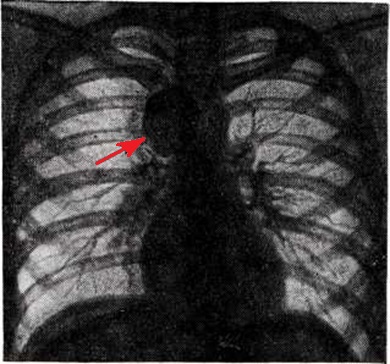

Рис. 2.

Рентгенограмма грудной клетки больного с ганглионевромой средостения (стрелкой указана ганглионеврома).

Рентгенологическая картина Ганглионеврома зависит от её локализации. Наиболее часто объектом рентгенологическое исследования является Ганглионеврома, растущая из элементов пограничного симпатического ствола и проникающая в паравертебральный отдел заднего средостения. На прямой рентгенограмме Ганглионеврома заднего средостения даёт однородное различных размеров затемнение полукруглой или полуовальной формы, тесно примыкающее к тени позвоночника. Очертания тени Ганглионеврома обычно чёткие и ровные (рисунок 2). В боковой проекции для Ганглионеврома характерна непосредственная близость к тени позвоночных концов рёбер. При затруднении определения локализации Ганглионеврома могут быть применены пневмомедиастинография (смотри) или искусственный пневмоторакс (смотри Пневмоторакс искусственный).

Ганглионеврома при больших размерах может оттеснять пищевод и трахею. В некоторых случаях Ганглионеврома раздвигает ребра или вызывает появление узур от давления прилежащих отделов позвонков. Обызвествление Ганглионеврома встречается редко. При малигнизации Ганглионеврома отмечается ее быстрое увеличение и деструкция прилежащих к ней рёбер и позвонков. При локализации Ганглионеврома в переднем средостении диагностика возможна лишь в тех случаях, когда рентгенологическое исследование дополняется пункционной биопсией под экраном. Особую разновидность Ганглионеврома составляют так наз. опухоли в виде песочных часов, состоящие из 2 узлов — меньшего, расположенного в позвоночном канале, и большего — в заднем средостении. При этом на снимках обычно определяется расширение соответствующего межпозвоночного отверстия. При Ганглионеврома надпочечника применяют также томографию (смотри) в условиях искусственного пневморетроперитонеума (смотри) и селективную ангиографию (смотри).